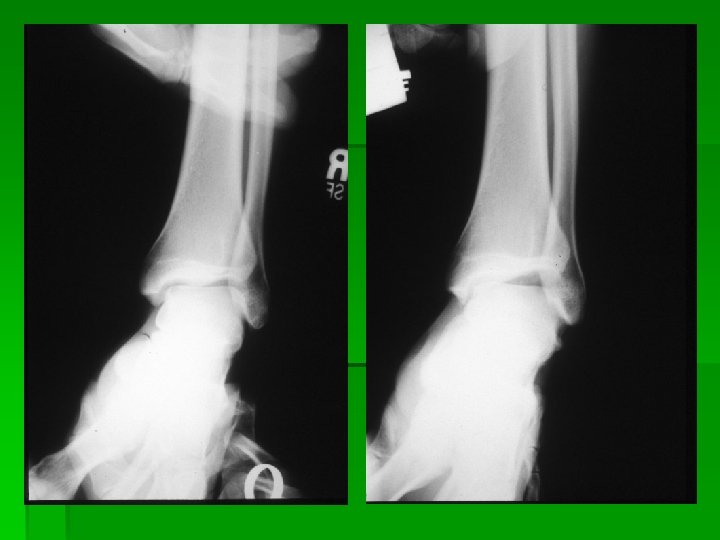

Ankle dislocation with no fractures. This takes a high degree of trauma and force. In this case this was generated as the result of a high flip off of a trampoline and impact with the ground. The ankle was in a plantar flexion and inverted position upon impact. This was an open dislocation.